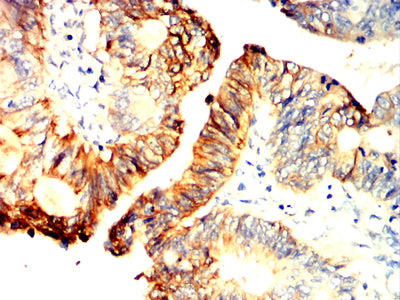

Immunohistochemical analysis of paraffin-embedded human renal carcinoma tissues using NOTCH2 mouse mAb with DAB staining.

Immunohistochemical analysis of paraffin-embedded human rectum cancer tissues using NOTCH2 mouse mAb with DAB staining.